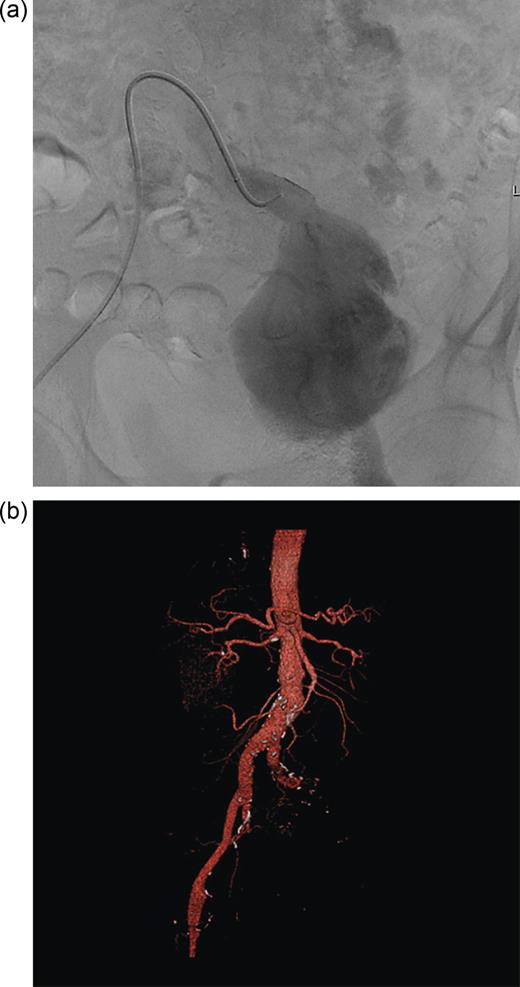

The radiologists proceeded to perform endovascular embolization of the left internal iliac to aid any further procedures. It was during direct catheterization of this aneurysm that it was noted to be blind ending with cross filling of the posterior division of the left internal iliac artery via collaterals from the right internal iliac artery (Figure 3a and b).

(a) Endovascular catheterization showing aneurysm to be blind ending. (b) 3D CT reconstruction showing blind ending aneurysm.